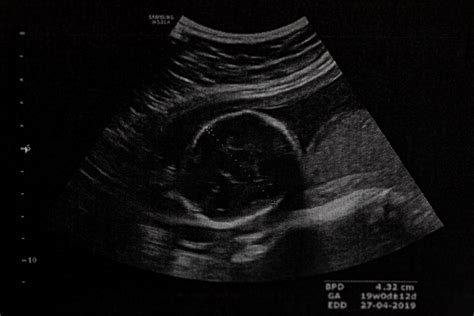

- Skríningové testy: V prvom a druhom trimestri tehotenstva sa vykonávajú neinvazívne biochemické vyšetrenia krvi matky a ultrazvukové vyšetrenie (napr. meranie tzv. šijového prejasnenia - NT). Tieto testy určujú pravdepodobnosť postihnutia plodu.

- Diagnostické testy: Pri zvýšenej pravdepodobnosti sa odporúčajú invazívne metódy ako amniocentéza (odber plodovej vody) alebo odber choriových klkov, ktoré priamo analyzujú chromozómy plodu s vysokou presnosťou (až 99,5 %). Tieto metódy však nesú malé riziko komplikácií.